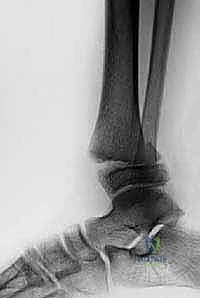

- الأشعة السينية (X-rays): هي الخطوة الأولى والأساسية. يتم التقاط صور من زوايا متعددة (أمامية، جانبية، ومائلة) لتقييم الكسر.

طريقة العلاج: يتم وضع ساق الطفل في جبس يمتد من تحت الركبة إلى أصابع القدم (أو فوق الركبة في بعض الحالات لمنع الدوران) لمدة تتراوح بين 4 إلى 6 أسابيع. يتطلب هذا العلاج متابعة أسبوعية بالأشعة للتأكد من عدم تحرك الكسر داخل الجبس.